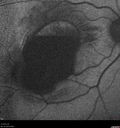

62 year old african american female with moderate chronic hypertension A few weeks ago she was at work and noticed a dark spot in the right eye. Since then it is not getting any better. She was out of town when it happened. VA OD: Dcc6’/200 Ncc20/400 VA OS: Dcc20/32 NccJ1

Macroaneurysm - Macular Hemorrhage - Branch Retinal Aterial Occlusion368 views62 year old African American female with chronic hypertension and vision loss for 2 weeks. VA is 20/40000000